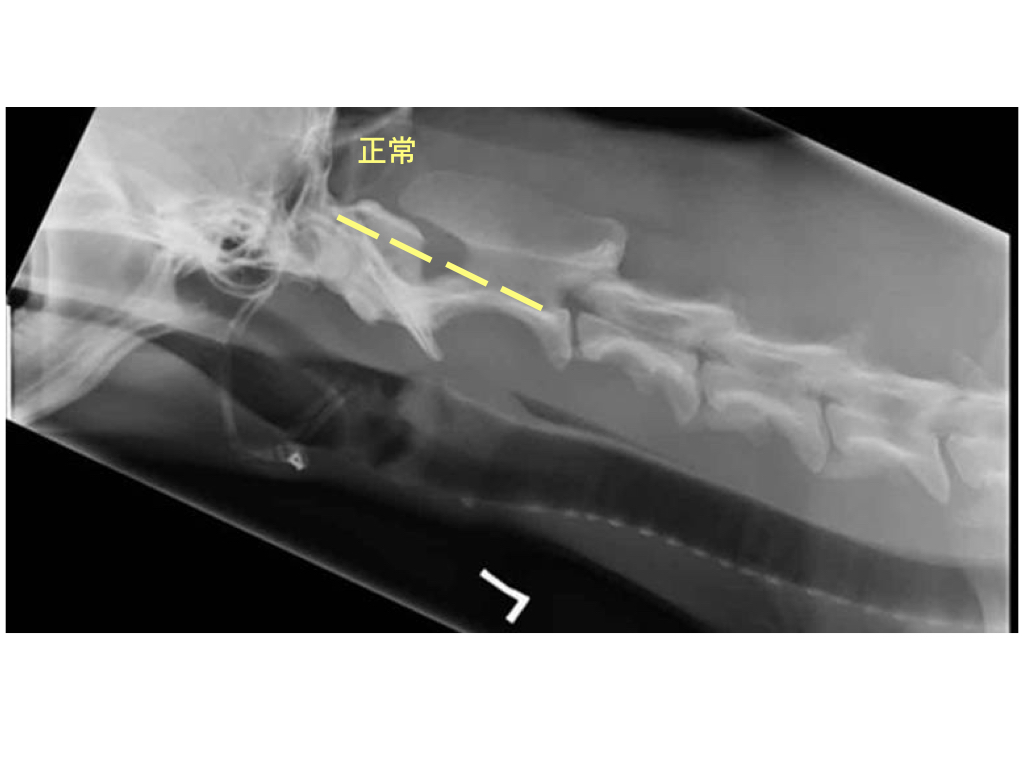

除了臨床症狀以外,獸醫師會進行完整的神經學檢查,並拍攝X光片。當要評估頸部是否有不穩定時,必須拍攝特殊角度的X光片,此時需要專業獸醫師來進行操作,避免在過程中造成頸部更不穩定的情況。在部分情況下,如神經症狀比較嚴重情況下,也須仰賴進階的電腦斷層診斷。